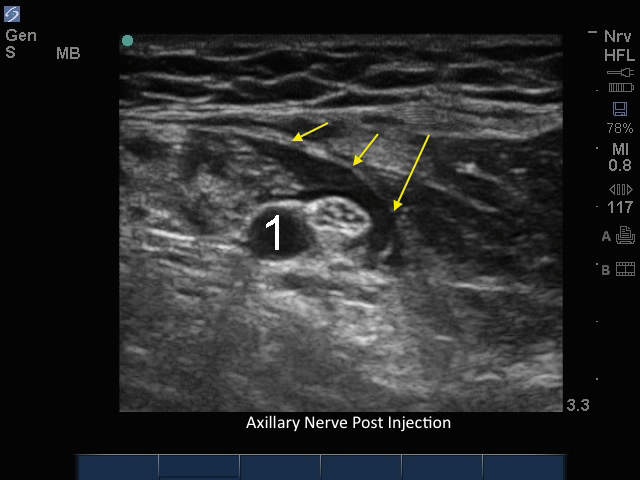

腋窩神経注射後

矢印:局所麻酔薬

動脈